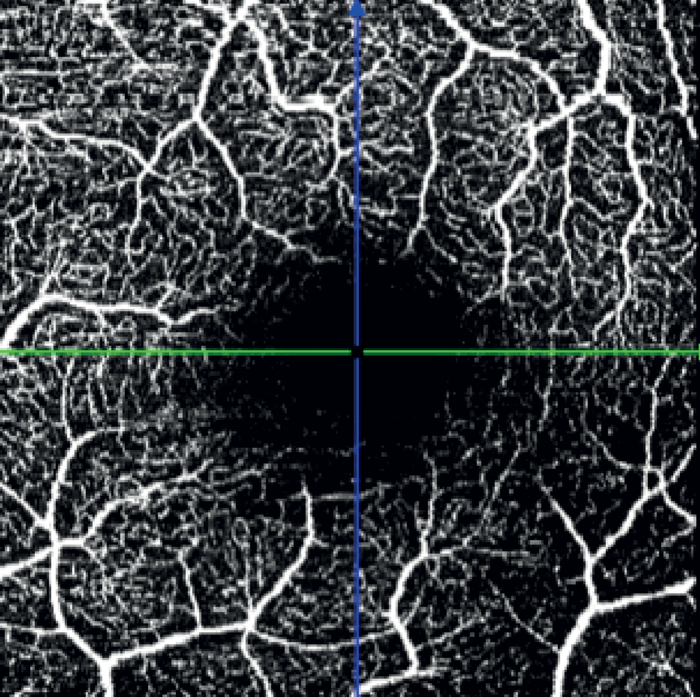

In the left eye – which had a mild inferotemporal RNFL thinning and a normal visual field – SPECTRALIS OCT Angiography revealed a wedge defect and corresponding profound capillary dropout around the optic nerve head (see Figure 8). This corresponded to capillary dropout in the inferior macula (see Figure 9).

Given the profound loss of vessel density as seen on OCTA in the left eye, an aggressive target IOP was set.